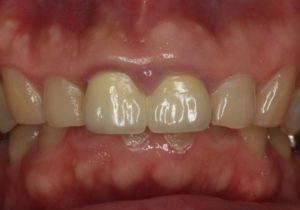

どのように変わったか、下の写真をご覧ください。

- 術前

- 術後